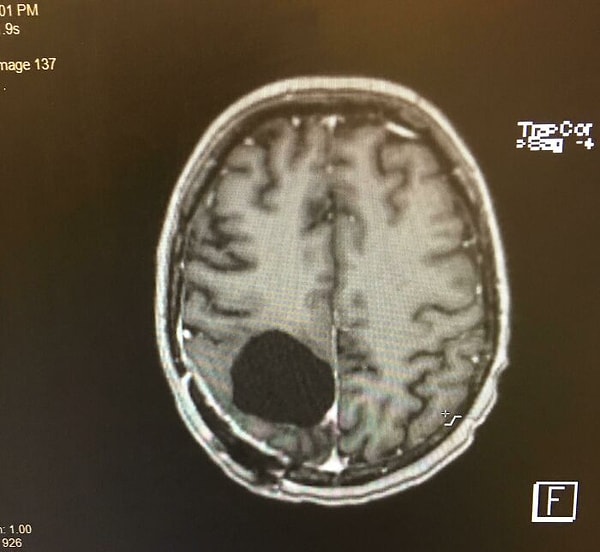

15. Мне удалили опухоль головного мозга, и теперь я немного рассеян...

16. Пересадка сердца! Плохое сердце выходит и новое входит!